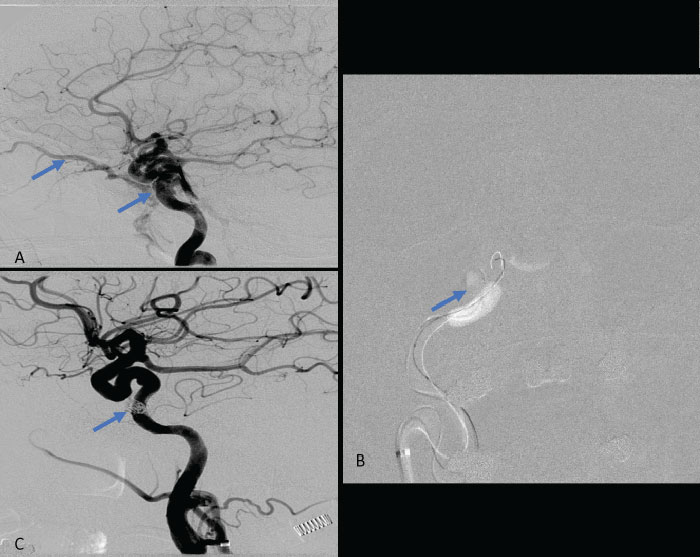

Collateral venous drainage into the orbit and skull base was observed (Fig. A). After successful cannulation of the direct aperture between the right carotid artery and the cavernous sinus, balloon-assisted coil embolization of the posterolateral compartment was performed until the fistula was closed (Fig. B and C). She experienced immediate cessation of her pulsatile tinnitus with the early improvement of the right VI nerve palsy and near-complete recovery of her vision within 6 weeks.

Figure: (A) Right ICA Cavernous Fistula with Venous Shunting (B) Balloon Assisted Coil Embolization (C) Fistula Cured Post Embolization

A 61-year-old woman who is otherwise healthy presented to her PCP with progressive right-sided pulsatile tinnitus for 4-6 weeks. Her PCP and ENT evaluated her extensively and prescribed multiple courses of steroids and subsequent unremarkable MRI and MRA imaging. She developed acute onset diplopia secondary to a new partial right VI nerve palsy several days prior to our evaluation. A cerebral angiogram confirmed the presence of a high flow direct fistula of the right internal carotid artery–right cavernous sinus.